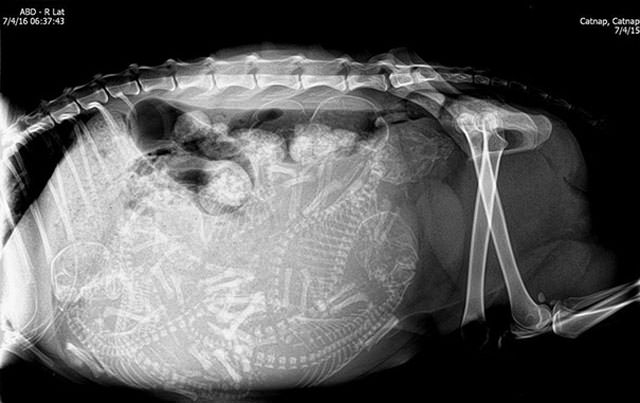

İnsanların ultrason görüntülerini görmeye hepimiz alışkınız. Ancak hamile hayvanların ultrason görüntüleri sizleri çok şaşırtacak.Kaplumbağa

İnsanların ultrason görüntülerini görmeye hepimiz alışkınız. Ancak hamile hayvanların ultrason görüntüleri sizleri çok şaşırtacak.